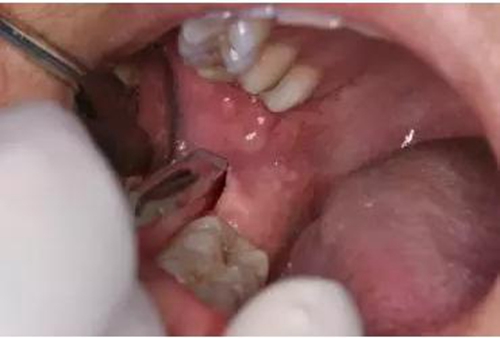

圖9.翻小瓣、用骨膜剝離器輕柔牽拉頰側(cè)齦瓣、暴露48合面

圖10.普通牙挺放置在48牙冠的近中根面與牙槽嵴頂之間,采用推力和挺力,挺松48.

圖11.以頰側(cè)骨板做支點(diǎn)、往上脫位